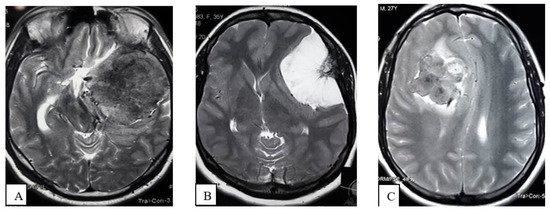

- Extrapial: Surgical cleavage plane lies outside the pia mater in more than two-thirds of the overall interface between tumor and cortex, regardless of whether an arachnoid membrane could be clearly identified (Figure 4A);

- Mixed: Cleavage plane lies outside the pia mater in more than one-third but less than two-thirds of overall interface (Figure 4B);

- Subpial: Tumor capsule exceeds the pia mater in more than two-thirds of the tumor cortex interface, and the surgeon was required to pass underneath the pia mater because of its incorporation into the tumor capsule (Figure 4C).